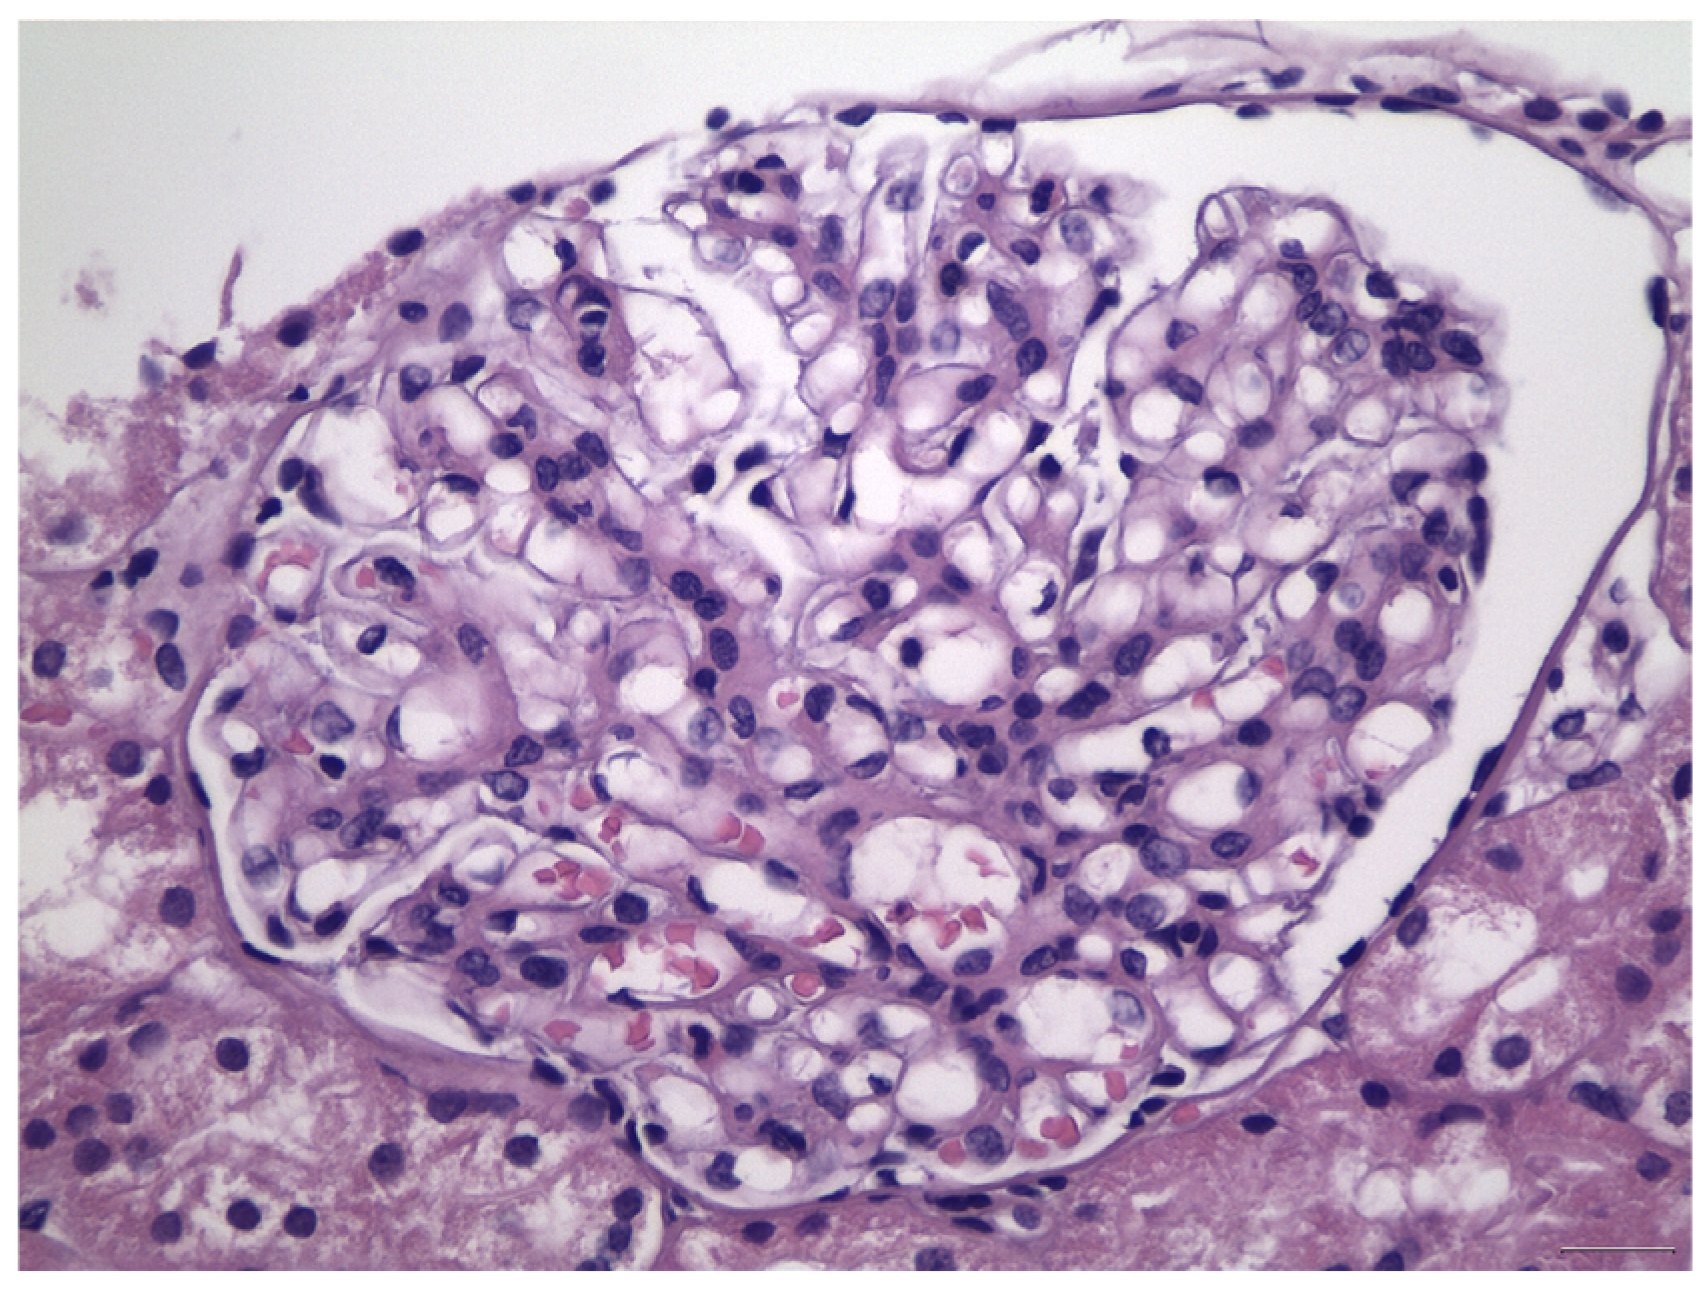

- Berger, J.; Hinglais, N. Intercapillary deposits of IgA-IgG. J. D’urologie Nephrol. 1968, 74, 694–695. [Google Scholar]

- Haas, M. Histologic subclassification of IgA nephropathy: A clinicopathologic study of 244 cases. Am. J. Kidney Dis. 1997, 29, 829–842. [Google Scholar] [CrossRef]

- Cattran, D.C.; Coppo, R.; Cook, H.T.; Feehally, J.; Roberts, I.S.D.; Troyanov, S.; Alpers, C.E.; Amore, A.; Barratt, J.; Berthoux, F.; et al. The Oxford classification of IgA nephropathy: Rationale, clinicopathological correlations, and classification. Kidney Int. 2009, 76, 534–545. [Google Scholar] [CrossRef] [PubMed]

- Roberts, I.S.D.; Cook, H.T.; Troyanov, S.; Alpers, C.E.; Amore, A.; Barratt, J.; Berthoux, F.; Bonsib, S.; Bruijn, J.A.; Cattran, D.C.; et al. The Oxford classification of IgA nephropathy: Pathology definitions, correlations, and reproducibility. Kidney Int. 2009, 76, 546–556. [Google Scholar] [CrossRef] [PubMed]

- Jennette, J.C.; Olson, J.L.; Silva, F.G.; D’Agati, V.D. Heptinstall’ s Pathology of the Kidney, 7th ed.; LWW: Philadelphia, PA, USA, 2015. [Google Scholar]